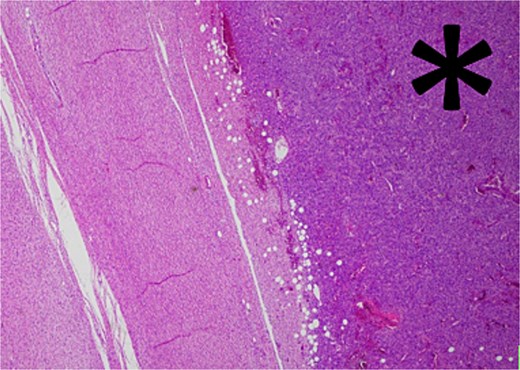

Histology revealed a multilobulated spindle cell lesion, with low- and high-grade areas, with an abrupt transition between these areas. There was an adjacent focus of adipose tissue with rare cytologic atypia suggestive of possible WDL, which indicated that the tumor mass may represent DDL. However, there was a single focus of lipoblasts identified, bringing up the differential of pleomorphic liposarcoma. Therefore, in situ hybridisation was performed and showed MDM2 amplification, which confirmed the diagnosis of DDL, with likely homologous lipoblastic morphology. The tumour was excised with clear margins (Figs 3–8).

Low-grade component with abrupt transition to high-grade component (asterisk).

The high-grade component demonstrates increased cellularity, hyperchromasia and moderate to marked pleomorphism including scattered multinucleate cells.